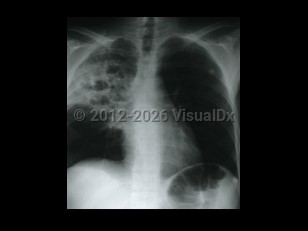

Chest pain, Pleural effusion, 50-59 year old Female

Pleural effusionPleural effusion

Hemothorax

Pulmonary empyema

Lung cancerLung cancer

TuberculosisTuberculosis